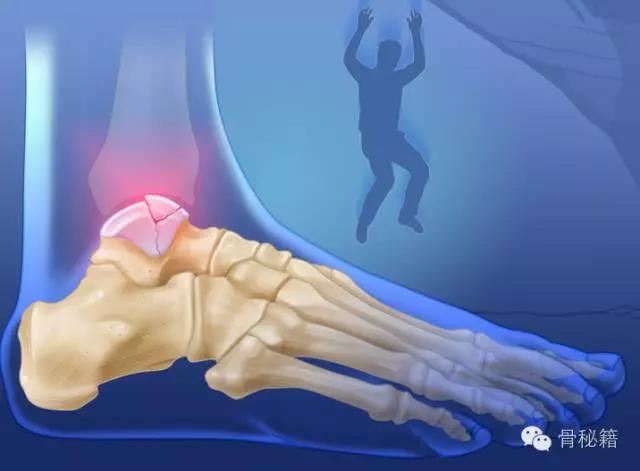

距骨----是一个很厉害的骨也是一个很烦人的骨

厉害在哪里?全身的重量都传导到它一个骨进行负重

损伤主要位于以下几个主要部分体、颈、后突、外突

还有一个就是血供的影响距骨很容易坏死就是血供遭到了破坏

当发生骨折脱位时,由于位移巨大,导致相应位移的血管损伤、最终导致距骨坏死所以距骨骨折的分型常用Hawkins分型距骨坏死率随分型严重程度逐渐增加